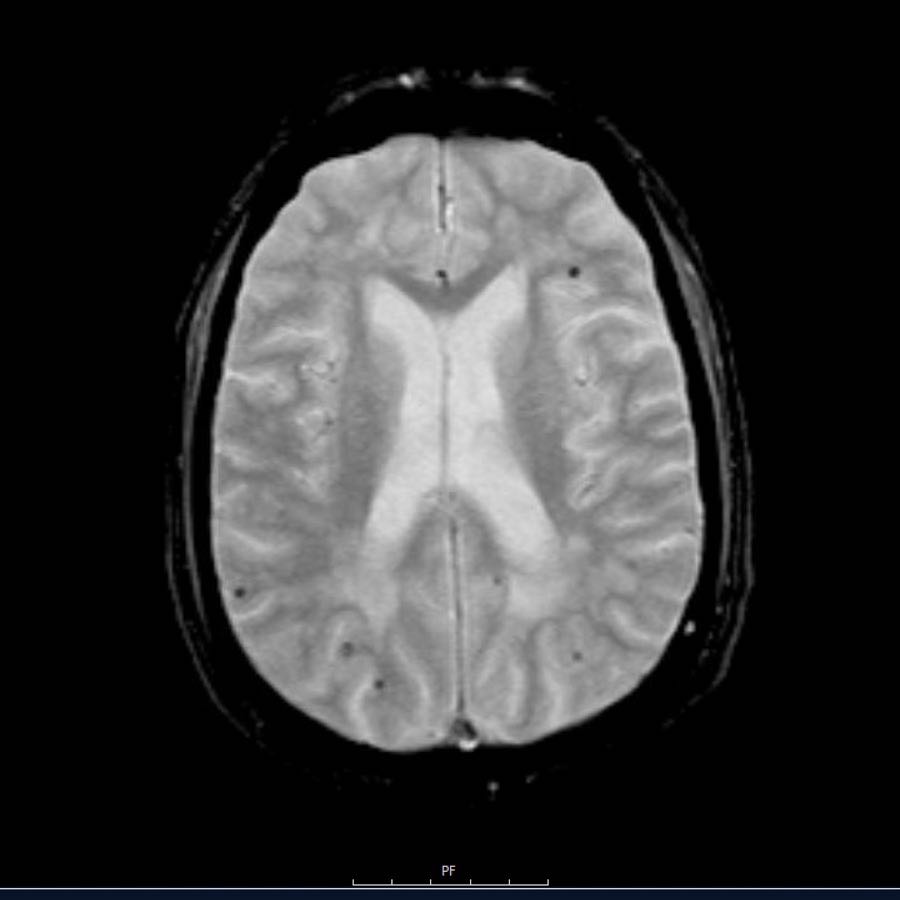

Các ổ xuất huyết nhỏ này còn được gọi là xuất huyết vi thể (microbleeds).

Lưu ý số lượng rất nhiều các ổ xuất huyết nhỏ này, phân bố chủ yếu ở vùng ngoại vi của não.